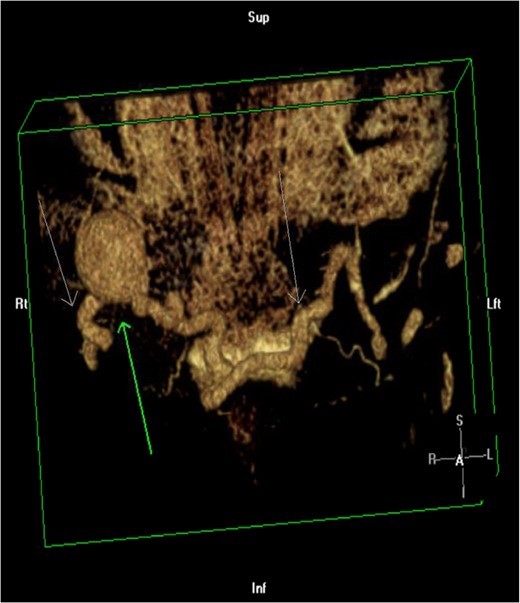

3D reconstruction of CTA of the abdomen/pelvis. Green arrow pointing up demonstrates an aneurysm in the anomalous saphenous vein connection. White arrows pointing down shows the tortuous connection of the greater saphenous veins.